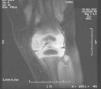

Se realizó RM al finalizar el tratamiento, en la que se observó una alteración en la intensidad de señal del cartílago epifisario del cóndilo femoral interno en relación con las secuelas de osteomielitis y artritis previamente conocidas, que en el momento actual no muestran edema ni derrame articular. (fig. 2). En el examen de orina postratamiento no se identificaron levaduras. En el seguimiento, los valores de velocidad de sedimentación globular (VSG) se mantuvieron normales.

Resonancia magnética de rodilla izquierda al finalizar el tratamiento antifúngico. Alteración en la intensidad de señal del cartílago epifisario del cóndilo femoral interno, en relación con secuelas de osteomielitis y artritis conocidas, sin edema ni derrame articular. Evolución favorable de artritis.